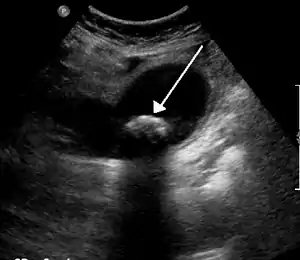

Cólica biliar é a ocorrência de dor quando uma pedra na vesícula biliar bloqueia temporariamente o ducto cístico.[1] Na maior parte dos casos a dor situa-se na parte superior direita do abdómen, podendo irradiar para o ombro.[2] A dor dura geralmente de uma a algumas horas.[1] É frequente manifestar-se depois de uma refeição farta ou durante a noite.[1] São também comuns ataques sucessivos.[3]

A formação de cálculos biliares tem origem na precipitação de cristais que se agregam para formar pedras. Os cálculos mais comuns são constituídos por colesterol.[4] Entre outros possíveis constituintes estão cálcio, bilirrubina, pigmentos ou cálculos mistos.[4]Entre outras condições que produzem sintomas semelhantes estão a apendicite, úlcera péptica, pancreatite e a doença de refluxo gastroesofágico.[1]